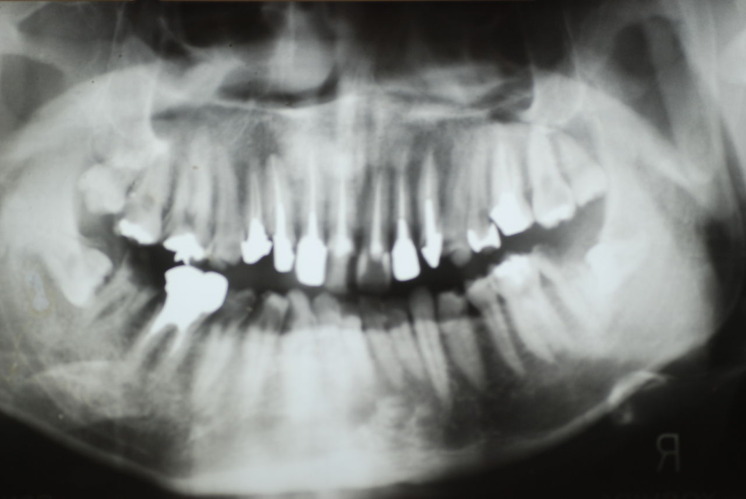

下記は患者に言われるままに血だらけでの不潔な状態で虫歯をとり埋めたようで全然適合していませんし、外れそうになっていました。

外したところです。中は虫歯のオンパレードでした。

適合が悪い銀歯が装着されていて更に虫歯の取残しにより歯髄炎症を起こして神経を取らざるをえなくなりました。神経を除去すれば痛みはなくなります。でもそれは死ぬことなのです。ほぼ寿命は半減したと考えるしかないのです。

まずは掃除の仕方を学ぶべきだったのです。環境をある程度良くしてから治療しないのでほぼ失敗に終わり、またハズレて虫歯により崩壊してしまうのです。